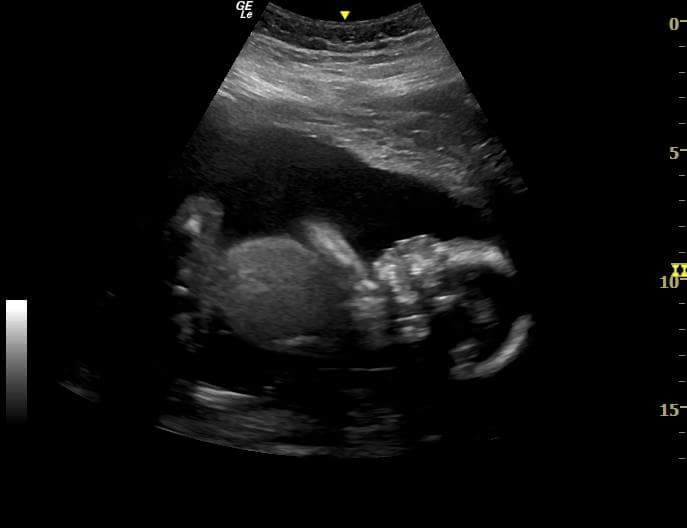

16w today, and found out during my ttts monitoring ultrasound this morning that i’m having two more GIRLS! i’m excited to go through all of dd1’s old baby clothes and see all of the cute outfits that will get to be used again. ultrasound tech joked that i must have had some intuition about it because i put on a pink shirt this morning,